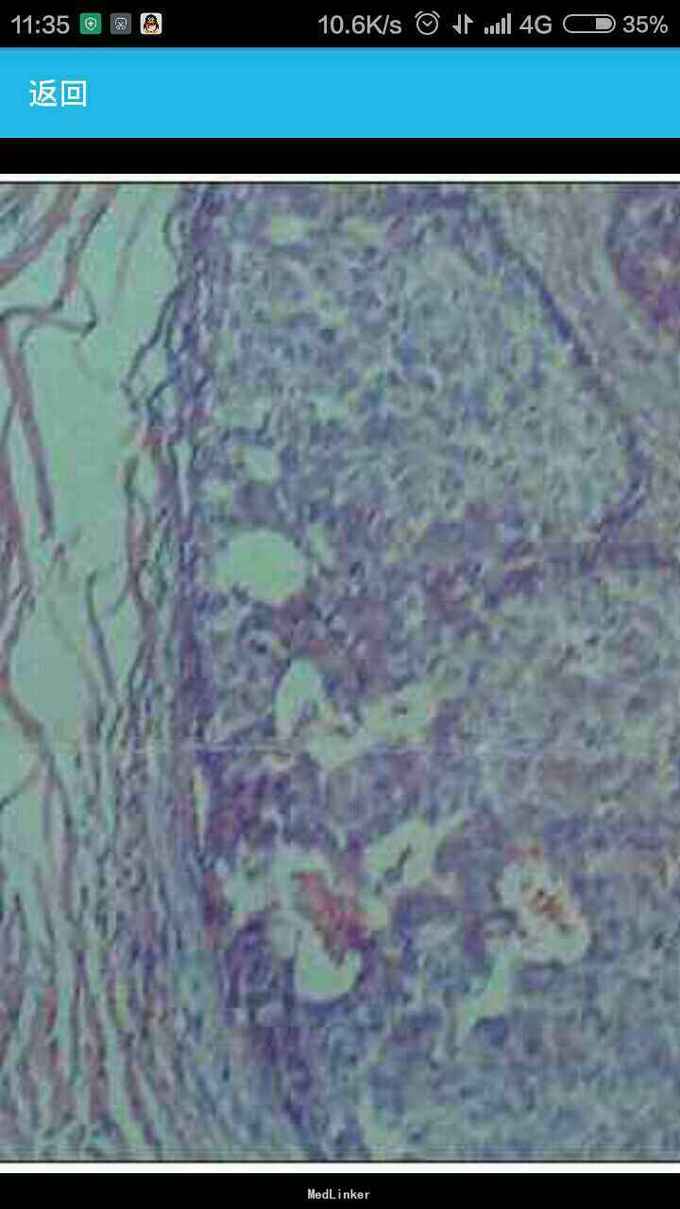

女性,60岁,因左 趾关节红肿、剧痛,红肿弥漫足背 23天来诊,不伴发热,无外伤史, 全身体检无明显异常。 胸片示,左侧前上纵隔占位性病变(图1)。胸部CT示,左侧前上纵隔内见5.7 cm×3.8 cm软组织肿块影,内见斑片状稍高密度影,境界不清(图2——5)。 实验室检查显示,血尿酸517.1 μmol/L(正常值180——357 μmol/L),临床诊断为“急性痛风”,为排除相关疾病作进一步检查。 印象:左侧前上纵隔占位(恶性肿瘤?畸胎瘤?)。 手术结果:肿瘤位于左前纵隔,大小约为8 cm×8 cm ×6 cm,质硬,表面光滑,与心包、无名静脉、肺门粘连(侵犯壁层、脏层、胸膜、肺门、心包、膈肌、膈神经,伴肿大淋巴结)。【病理结果示】(图6):肿块9 cm×6 cm×4 cm,侵犯周围脂肪组织,伴神经内分泌分化。肿块标记:CD5(+)、CD117(+)、嗜铬粒蛋白A(CgA)灶(+)、突触素(Syn,+)、CD56 (-)、细胞增殖因子Ki-67约20%(+)。【诊断】胸腺鳞状细胞癌Ⅱ——Ⅲ级,伴神经内分泌分化。